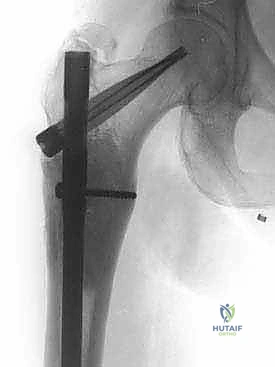

نقائل العظم الفخذي هي أورام ثانوية تنتشر إلى عظم الفخذ، مسببة الألم والكسور. يشمل علاجها الجراحي استعادة الوظيفة وتخفيف الألم من خلال التجريف والتثبيت بمسامير نخاعية أو الاستئصال وإعادة البناء بأطراف صناعية، ويتم ذلك على يد خبراء مثل الأستاذ الدكتور محمد هطيف في صنعاء.

الخلاصة الطبية السريعة: نقائل العظم الفخذي هي أورام ثانوية تنتشر إلى عظم الفخذ قادمة من أورام أولية (مثل الثدي، البروستاتا، الرئة، الكلى، أو الغدة الدرقية)، مسببة الألم المبرح والكسور المرضية التي تقعد المريض عن الحركة. يشمل العلاج الجراحي المتقدم استعادة الوظيفة، الحفاظ على استقلالية المريض، وتخفيف الألم بشكل جذري من خلال تقنيات مثل التجريف والتثبيت بمسامير نخاعية مع الأسمنت العظمي، أو الاستئصال الواسع للورم وإعادة البناء بأطراف صناعية كبرى (Megaprosthesis). يتم إجراء هذه الجراحات المعقدة بأعلى نسب النجاح على يد خبراء جراحة العظام والأورام، وعلى رأسهم الأستاذ الدكتور محمد هطيف في العاصمة اليمنية صنعاء، والذي يجمع بين الخبرة الأكاديمية والمهارة الجراحية الدقيقة.